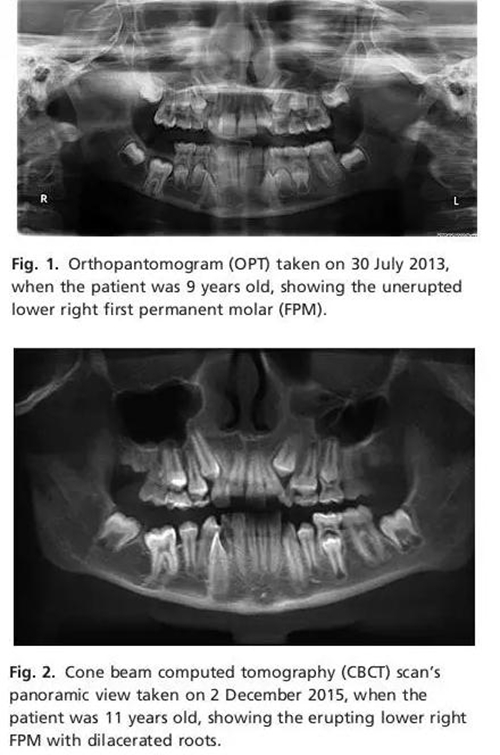

2013年7月13日正畸??漆t(yī)師給患者拍攝全景片。全景片示LR6存在但未萌,根尖接近下頜骨下緣。近遠(yuǎn)中根發(fā)育至75%左右,根尖孔未閉合,接近下牙槽神經(jīng)管??梢杂^察到牙囊所在的位置稍微增大但未形成囊腫,牙囊近中位于右下頜第二乳磨牙下方。牙列中其他恒牙萌出正常。

口內(nèi)檢查及影像學(xué)檢查表示LR6萌出失敗,診斷為IFE。要求患者拍攝CBCT以明確LR6牙根與下牙槽神經(jīng)管的位置關(guān)系,考慮是否手術(shù)治療。

患者3個(gè)月后復(fù)診拍攝CBCT。臨床檢查發(fā)現(xiàn)LR6近中牙尖開始萌出,遠(yuǎn)中牙尖被牙齦覆蓋。影像學(xué)檢查示LR6在牙槽骨中移動(dòng),牙根位于LR5和LR7之間?;谝陨蠙z查決定放棄手術(shù)治療,繼續(xù)監(jiān)測(cè)患者牙列發(fā)育情況。

本章介紹了11女性患者單側(cè)FPM未萌的病例。LR6是口內(nèi)唯一受累牙,并且可以清楚的看到患牙冠方的萌出通道。CBCT顯示牙根彎曲。這種現(xiàn)象可能與暫時(shí)牙槽骨粘連然后萌出有關(guān)。臨床上很少見到FPM患牙5年后恢復(fù)萌出能力,萌出到正常位置。